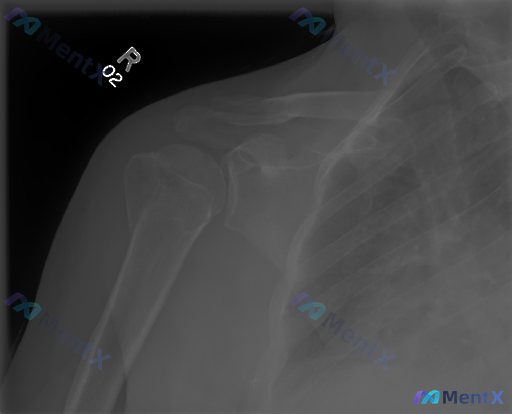

整理到一份有意思的影像讨论素材: - 影像:右肩关节正位X光 - 初看报告:骨结构完整,皮质连续,关节对位好,无明显骨折/脱位/钙化/退行性变 - 但核心提示:存在异常 这种“影像初筛阴性但临床/提示阳性”的情况最容易踩坑。 大家觉得如果要往下走,首先会重点怀疑哪个方向?下一步最想补什么信息或检查?